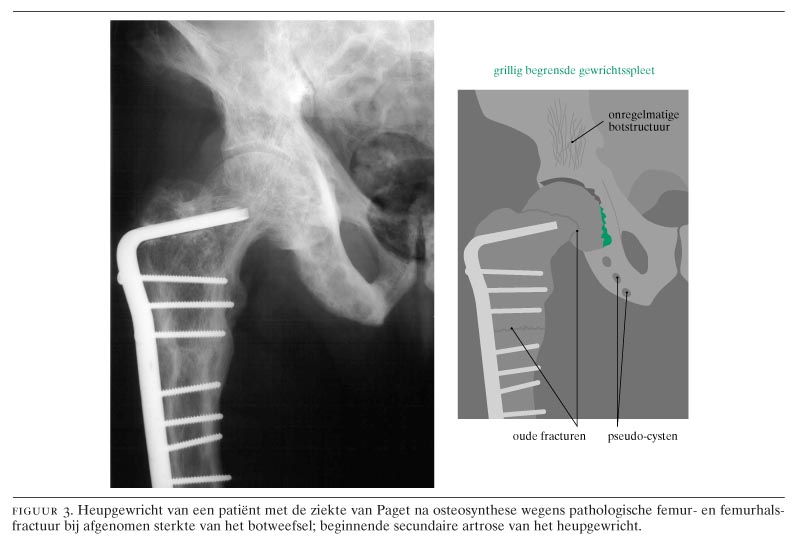

Ziekte van Paget. Osteïtis deformans. Vervormingen en verdikkingen van het bot door verhoogde botafbraak en -aanmaak. Komt vooral voor in bekken, wervelzuil, dijbeenderen en schedel. Op deze pagina. Afspraken. Symptomen. Behandeling. Onderzoeken en diagnose. Specialisten. Afspraken. Centrum voor metabole botziekten.. Leeftijd. Voorgeschiedenis van borstkanker of borstafwijkingen. Familie met borstkanker. Genetische factoren. Dicht borstweefsel. Blootstelling aan straling. Overgewicht. Hormoonvervangingstherapie. Alcohol. Symptomen van de ziekte van Paget. Schilfering van de tepelhuid en ingetrokken tepels. Hard knobbeltje in de borst. Onderzoek en diagnose.